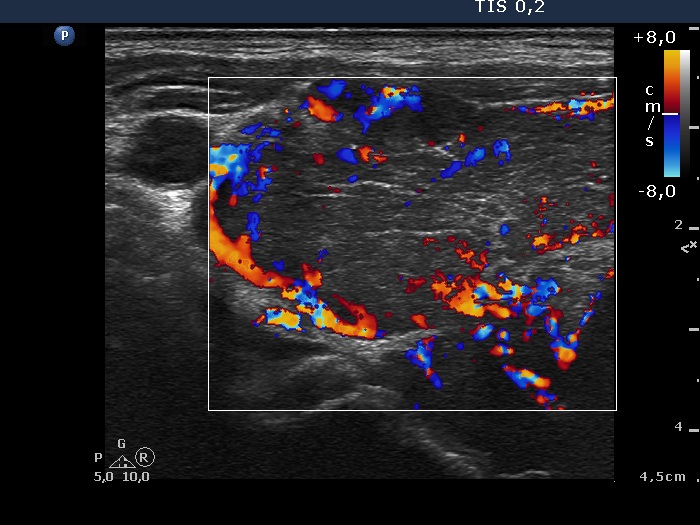

Ultrasonography. Both lobes were extremely enlarged, the dimensions of the right lobe was 75x55x120 mm. The whole thyroid was severely hypoechogenic, inhomogeneous. The vascularization was irregularly increased.